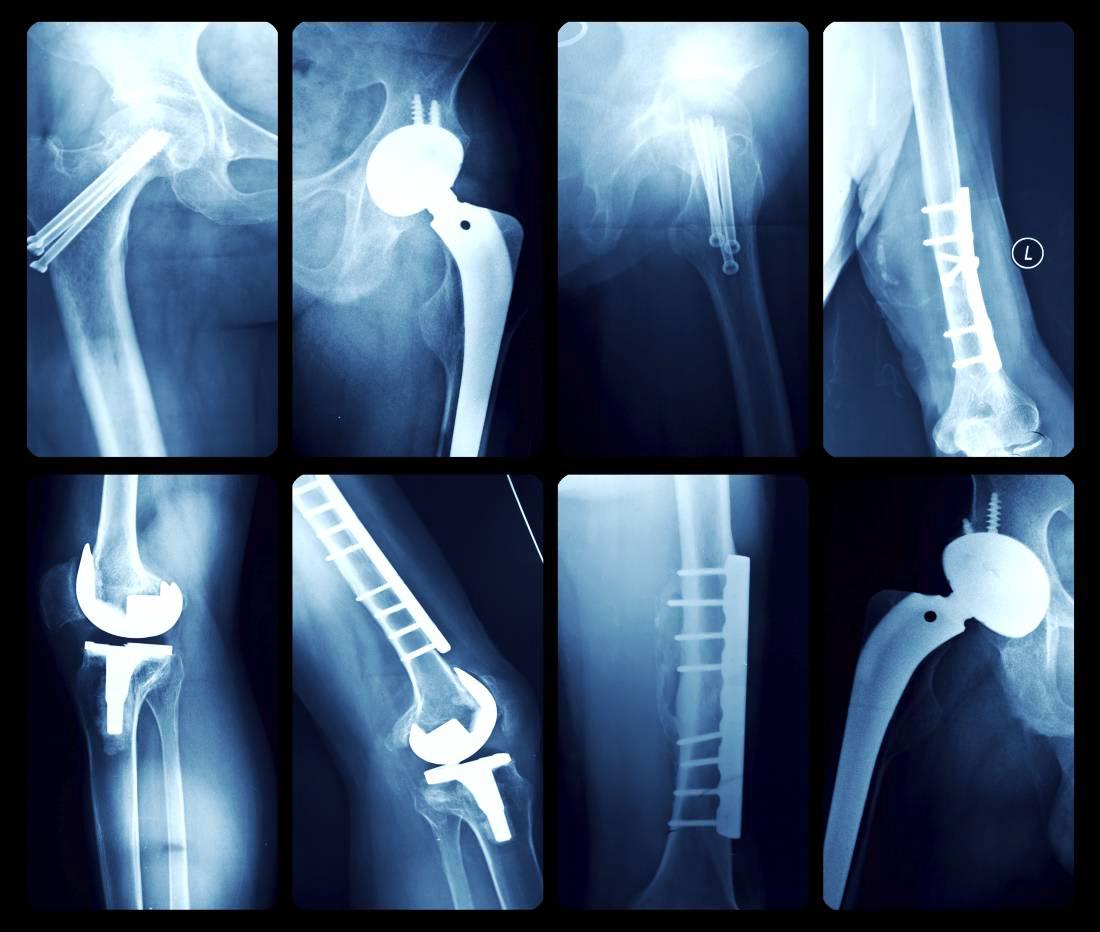

Margaret Hawkins: “What about a situation where a person says they are in great pain, but the X-ray doesn’t show huge damage?”Stuart Edwards: “In situations like this, it’s important to emphasise that it is the patient we are treating, not the X-ray. I usually suggest what I call a diagnostic and therapeutic hip injection. If this eradicates their pain over six to eight weeks it would be a stronger indication for them to have a hip replacement operation. I would also send them for an MRI scan as it will emphasise any wear and tear to the hip, but X-rays are generally the gold standard for showing osteoarthritis damage.” MH: “How long will the hip replacement last?”SE: “About 15 years and maybe longer, as the technology is improving all the time.” MH: “What’s the most common age to have one done?”SE: “The most common age is the early to mid-60s. Over the last decade, the age of having such operations has reduced because technology has improved and patients’ expectations have increased.” MH: “What are the risk factors for osteoarthritis of the hip?”SE: “Obesity is a factor, but a family history of osteoarthritis can be a bigger one. There is also a congenital condition called dysplasia, where the socket didn’t form properly, and approximately 40% of women under 50 who have arthritis have a degree of dysplasia.” MH: “What occupations are affected the most?”SE: “It’s either young sportsmen, who have had lots of knocks and groin strains over the years and then develop problems in their mid-30s or 40s, or people like farmers, whose work has involved heavy daily lifting which has led to a repetitive stress injury of the hip joint.” MH: “Are there different types of hip replacements?”SE: “Yes, cemented and uncemented. With the cemented hip, a titanium stem is inserted into the thigh bone and fixed using an acrylic cement. That’s the type of operation mostly done in northern Europe, but the uncemented type, more common in the US, is now becoming more popular. The idea behind the uncemented procedure is that the bone grows into parts of the [titanium] stem that’s inserted into the thigh bone, so it seems to be more biological. It’s also a slightly quicker operation. I do both kinds of operations. I use cemented hips in the more elderly population that have wider thigh bones, as it is easier to get a complete fit. The uncemented approach I use in younger patients in the hope that, biologically, it may last them longer.”

“An incision of about 15cm is made, your hip is dislocated from the socket, the femoral [thigh bone] head is removed, the socket is exposed, the circumference of it is cleaned and it is then shaped into a hemisphere so that the new socket can fit snugly.

“The worn cartilage is then removed in order to get down to good-quality bone. In the uncemented operation, the hole the surgeon makes is 1mm smaller than the trial shell.

“If there is a tight fit, the definitive shell, which is made of titanium, is inserted. This shell has a very rough surface on the back of it, which allows bone to grow into it. Then the shell is checked for stability. Sometimes screws are used to make the socket more stable. After this, a liner made of plastic or ceramic, with a self-locking mechanism, is put inside this [socket] shell.

“The surgeon next concentrates on the femoral [the thigh bone] side. A series of increasing sized broaches are inserted into the thigh bone.

“A sleeve is then put on top of the broach and a ball on top of that and the hip is then put back into the joint.

“If the hip is stable and the soft tissue tension is correct, the definitive implants are selected and inserted. The different layers of the wound are then sewn up and the patient is transferred to the recovery room.”